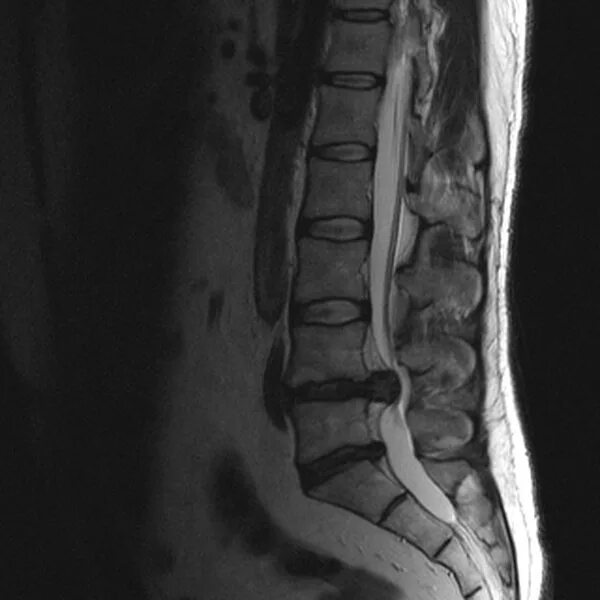

Как выглядит грыжа позвоночника на мрт